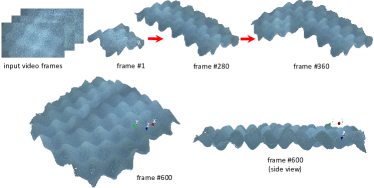

We employ the truncated signed distance field (TSDF) method [37] to mosaic the raw 3D point cloud generated from pixel disparities results of stereo matching and the camera calibration parameters to obtain the extended 3D model of the tissue surface, as shown in Fig. 3. The prerequisite to perform TSDF is to align the raw 3D point cloud accurately, which is equivalent to the estimation of camera motion in this video-based 3D reconstruction problem. As shown in Fig. 4, conventional iterative closest points (ICP)-based model alignment is difficult to handle smooth tissue surfaces. Another way to align models is based on image feature points matching. However, due to the low texture and varying illumination condition, feature matching is challenging and a large amount of outliers may exist. To overcome these problems, we propose a novel SLAM method that consists of fast and robust algorithms to handle the large percentage of feature matching outliers in real-time.

III-E GPU-based TSDF Mosaicking

The basic idea of TSDF is to take the average value of the 3D coordinates of an area if it is observed multiple times, which is more accurate than the results of a single observation. Raw 3D point cloud can be obtained from key video frames by using our stereo matching method. We incrementally mosaic the stereo matching results to generate the extended tissue surface model based on the camera motion estimation results of SLAM. The extended tissue surface models are also in the form of 3D point clouds. Because we aim to obtain high resolution textures to provide better surgical navigation, the extended surface model usually include millions of points and traditional volume-based TSDF method may take too large amount of computer memory. To avoid this problem, we store the 3D coordinate and the RGB color for each point in the GPU memory without using volume grids. To build correspondences between the extended surface model and the current stereo matching results, we project the extended surface model to the current imaging plane according to the camera pose estimation results. This rasterize process is performed by using GPU parallel computation and is fast. For each pixel with a valid depth value in the stereo matching results, the related point in the extended surface model is merged with the stereo matching results by using the TSDF method. Pixels that are not covered by the reprojection are considered as new points and will be added to the extended surface model.